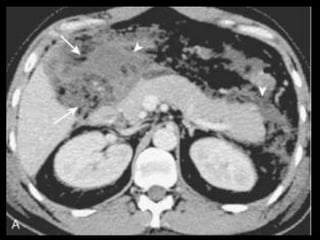

PANCREATITE AGUDA LEVE

Achados na TC

Glândula normal ou minimamente aumentada;

Atenuação baixa ou heterogênea, devido ao

edema intersticial, e um contorno irregular;

Tecido adiposo peripancreático pode se mostrar

normal ou indistinto devido à inflamação;

É comum o envolvimento difuso, mas podem haver

formas focais;

Após contraste: intensificação uniforme da

glândula devido à rede capilar intacta com

vasodilatação.